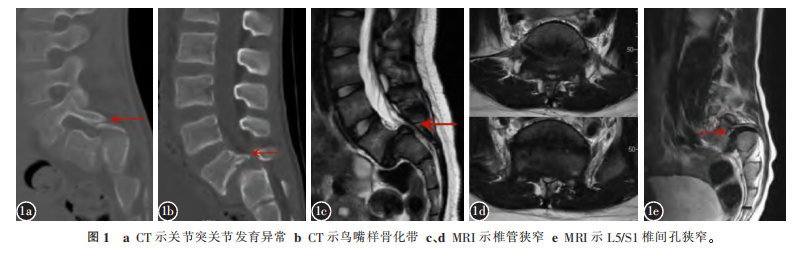

矢状位评估 发育不良性腰椎滑脱往往存在腰骶部后凸畸形,为维持平衡进而腰椎前凸代偿性增加;若无法通过腰椎前凸代偿,则依靠胸椎后凸减小甚至胸椎前凸再次代偿,此时会继发出现颈椎后凸。按照Hresko标准,发育不良性腰椎滑脱患者存在脊柱-骨盆失衡比例高达92%,而存在颈椎后凸的比例则高达70.8%。CT可清晰显示腰骶部发育不良形态,包括关节突关节更加扁平及矢状位角度变大(图1a),椎板变薄乃至缺如,横突短小等。同时也清晰显示因滑脱产生的继发性改变,如S1上终板穹窿样变、L5梯形变、峡部延长等,大部分患者因L5向前滑移导致L5/S1椎间盘纤维环于S1附着处牵拉而出现鸟嘴样骨化牵拉带(图1b)。MRI则可发现患者神经受压主要发生在S1后上缘与L5椎板之间,即后凸顶点水平,此处马尾神经受压最严重(图1c、1d);其次就是椎间孔区域,这是由于L5前滑脱导致椎间孔狭窄所致(图1e)。